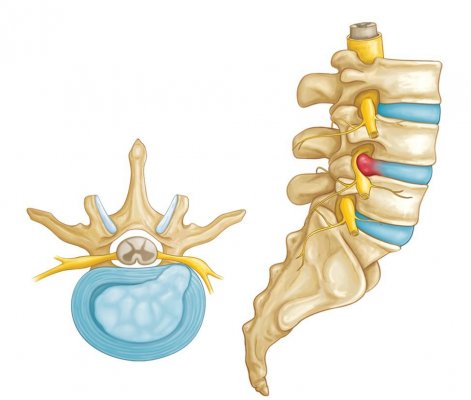

Ako nás platnička začne bolieť

Každá platnička je jedinečná a veľmi dobre navrhnutá štruktúra v našej chrbtici. Je dostatočne silná na to aby ustála ohromné sily v rôznych pohybových rovinách, no pritom je stále veľmi dobre… Viac

Čo je degeneratívne ochorenie platničiek?

Degeneratívne ochorenie platničiek je najčastejšou príčinou bolestí krížovej chrbtice a bolestí krku, a taktiež jednou z najviac nepochopených chorôb. Jednoducho povedané, degeneratívne ochorenie… Viac